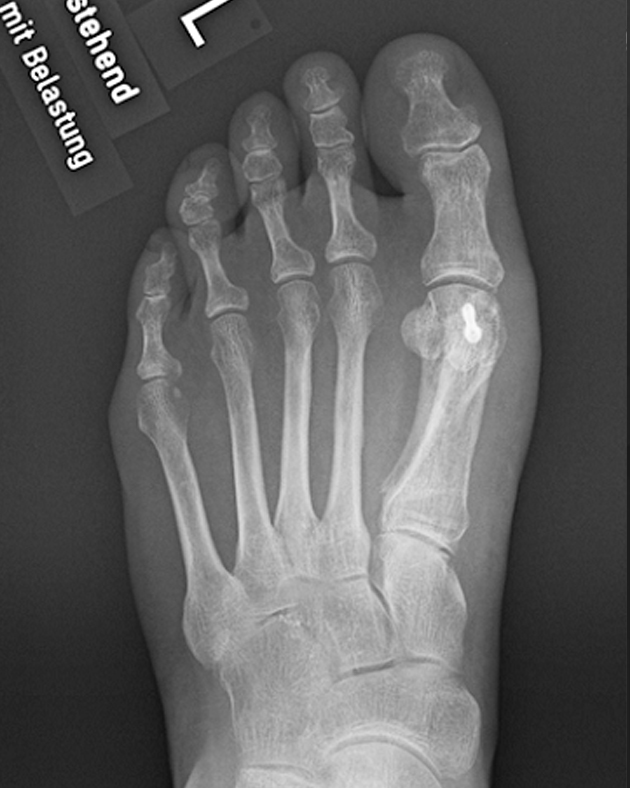

Hallux valgus Operation from www.klinik-impuls.ch

Hallux valgus Operation Lies Erfahrungsberichte von Patienten, die ähnliche Schmerzen nach ihrer Operation hatten Mein Zeh ist so gerade und steif, dass das Tragen von High Heels unmöglich ist! Selbst in normalen Alltagsschuhen tut es drücken. Diese OP zielt darauf ab, die Hallux valgus Deformität zu korrigieren, die Balance des Fußes wiederherzustellen und die Schmerzen zu lindern